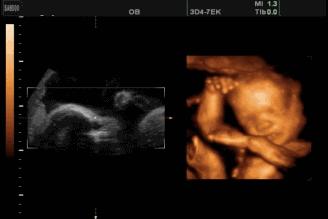

怀孕5个月,也就是孕20周前后。此时处于孕中期,正是胎动开始活跃的时候。胎儿的发育指标,如下:

1,胎儿的体重:290克左右;胎儿的体长:大约17厘米。

2,胎儿的发育特征:孕5月,胎儿软骨已经发育成骨骼;脂肪开始发育,皮脂腺开始分泌胎脂。这薄薄的一层胎脂将胎儿与羊水隔离开来,起到了保护胎儿和调节体温的作用;

孕5月,胎儿感觉器官神经细胞也开始分化发育,胎儿的味蕾已经发育完成;胎儿的脐带增粗变厚,更加坚固了。

3,胎动变化:孕5月,胎儿的胎动开始活跃了。打哈欠,打嗝,吞咽,吮吸,翻滚,跳跃,伸拳踢腿,等等这些胎动都已经出现。如果你平时忙于工作,或者前期对胎动不是十分敏感,那么现在你已经能真切地感受到胎儿在你肚子里面撒欢啦!